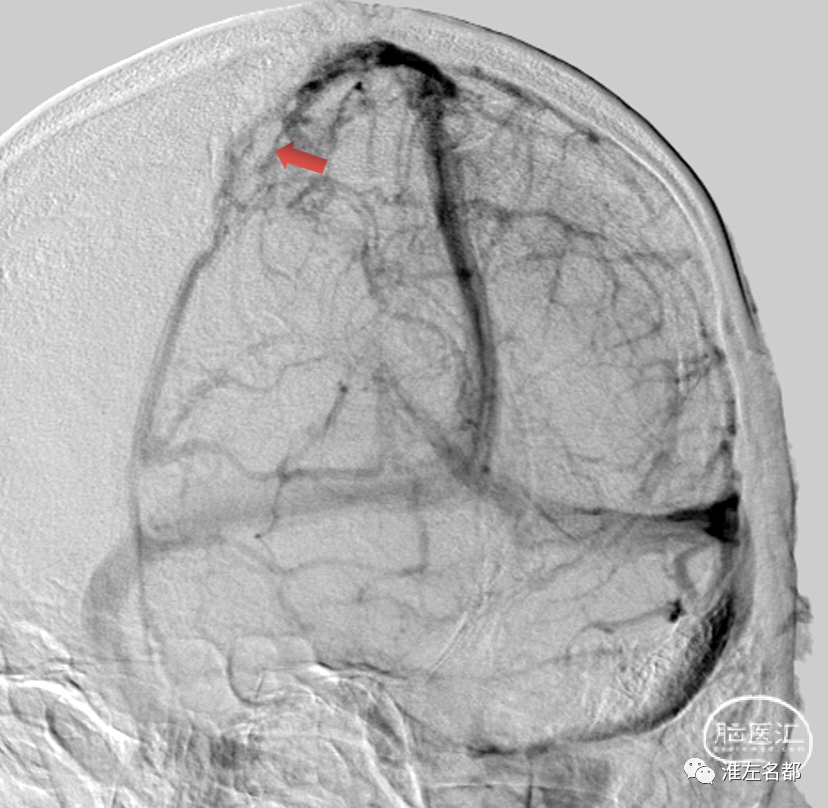

经颈动脉造影(斜位):

局部上矢状窦血栓充盈缺损,管腔狭窄。

经右侧颈动脉造影(正位):

右侧横窦远端、乙状窦和右侧颈内静脉远段显影不清,提示血栓闭塞。